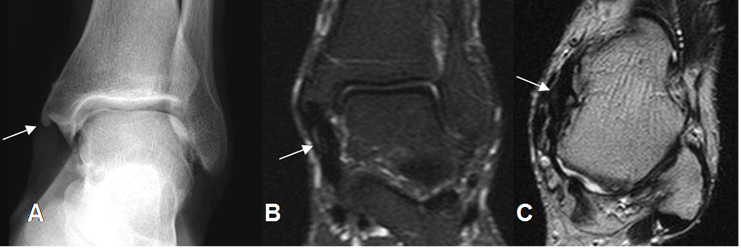

Fig 66. Lesión ligamentaria crónica.

A: Rx AP. Calcificación en el borde inferior del maléolo interno y prominencia de los tejidos blandos.

B: RM coronal en STIR y C: RM axial en T2. Engrosamiento del ligamento tibiocalcáneo (Flechas), por lesión crónica, sin signos de ruptura completa.